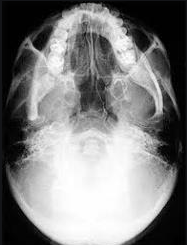

- Chụp X-quang Hirtz (chụp x quang tư thế cằm- đỉnh phim): giúp nhận biết tình trạng của xoang sàng trước, xoang sàng sau và xoang bướm.

2.2. Chụp X-quang Hirtz (chụp x quang tư thế cằm- đỉnh phim) thực hiện như thế nào?

Chụp X-quang Hirtz được thực hiện khi người bệnh được chẩn đoán bệnh viêm xoang sàng trước, viêm xoang sàng sau hoặc viêm xoang bướm. Ngoài ra, chụp X-quang Hirtz còn cung cấp chi tiết việc đánh giá tầng trước đáy sọ, vùng cánh bướm.

Để chụp X-quang Hirtz người bệnh sẽ được hướng dẫn nằm ở tư thế ngửa đầu sao cho đầu thả khỏi thành bàn để đỉnh đầu chạm vào phim, tia X đi từ trên xuống dưới.

Để thu được hình ảnh chuẩn xác, phục vụ tốt cho việc chẩn đoán, phim phải được đặt cân đối 2 bên phải và trái. Vách ngăn mũi chiếu thẳng giữa 2 răng số 1. Hình chiếu hai xoang sàng trước và sau trên cùng một bình diện, mốc phân định là khe 2 răng hàm số 6 và 7. Cung hàm trên và hàm dưới trùng nhau thành một hình vòng cung.

Trong điều kiện bình thường, hình ảnh các xoang sàng trước và sau sáng đều, các vách ngăn của các tế bào sáng rõ.

Nếu xoang mắc bệnh lý, các tế bào sàng mờ đều hoặc đặc do có mủ, niêm mạc dày, polyp trong xoang. Nếu các vách ngăn sàng không rõ, bị mất đi hoặc bị phá hủy, có thể người bệnh bị polyp mũi hoặc u ác tính.